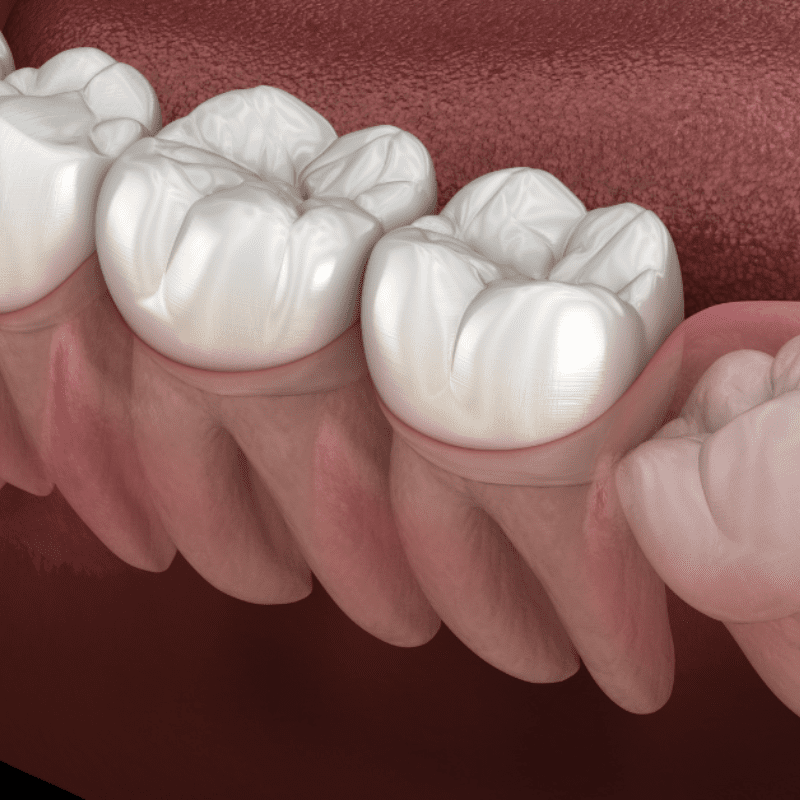

Wisdom teeth are the third and final set of molars that come in, usually between the ages of 17 and 25. As adult teeth naturally only come with 32 slots, when the 32nd tooth arrives, there isn’t always enough room for it, causing what is known as “impaction.”

If left untreated, neglected, impacted wisdom teeth can lead to a variety of dental problems and even other issues like misalignment of other teeth. However, by having them removed, you could reap several oral health benefits!